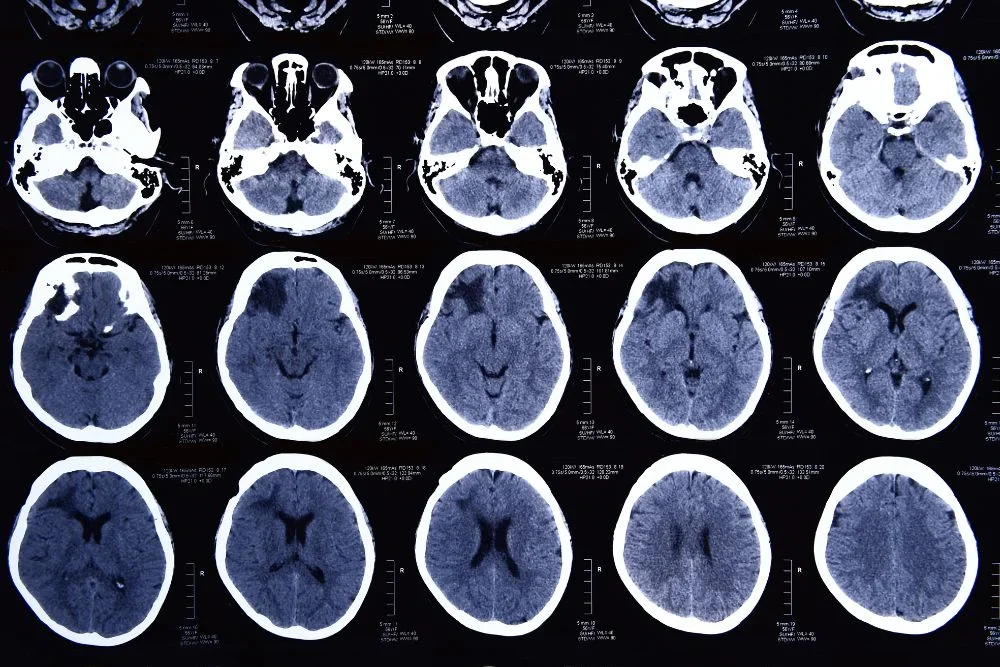

La Tomografía de Senos Paranasales es un procedimiento diagnóstico no invasivo que utiliza imágenes de alta resolución para evaluar los senos paranasales. Estos, son espacios llenos de aire se encuentran alrededor de la nariz y los ojos. La tomografía nos permite obtener imágenes detalladas de esta área, lo que ayuda a nuestros especialistas a identificar y diagnosticar diversas afecciones, como sinusitis crónica, pólipos nasales, obstrucciones o infecciones.